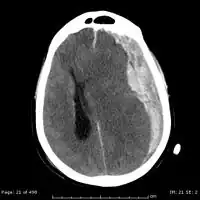

Chronic subdural after treatment with burr holes

On a CT scan, subdural hematomas are classically crescent-shaped, with a concave surface away from the skull. However, they can have a convex appearance, especially in the early stages of bleeding. This may cause difficulty in distinguishing between subdural and epidural hemorrhages. A more reliable indicator of subdural hemorrhage is its involvement of a larger portion of the cerebral hemisphere. Subdural blood can also be seen as a layering density along the tentorium cerebelli. This can be a chronic, stable process, since the feeding system is low-pressure. In such cases, subtle signs of bleeding—such as effacement of sulci or medial displacement of the junction between gray matter and white matter—may be apparent.

Fresh subdural bleeding is hyperdense, but becomes more hypodense over time due to dissolution of cellular elements. After 3–14 days, the bleeding becomes isodense with brain tissue and may therefore be missed.[22] Subsequently, it will become more hypodense than brain tissue.